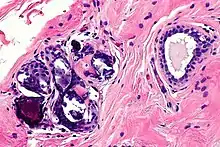

Around 1.5 million women have breast implant surgeries per year.[15] Yet the side effects of the fat transplant can be severe and cause irreversible damage to the patient's body. The most well-known side effects are foreign body sensation, calcification, fat cell necrosis, capsular construction, rupture, cysts and some fat cells leaving the implanted area.

In most cases, calcification and cysts are the biggest threat of breast augmentation surgery. Fat stem cells failed to pick up a new blood supply will die and be removed from the body by immune cells. However, when this clearing process miss removing dead cells the cluster will lead to calcification and cysts formation. These are visible on the breast as lump sometimes and are more dangerous when these un-picked up dead cells are detected as cancer cells which disturbs accurate diagnosis of breast cancer. The calcified tissue will be diagnosed as a 'benign' cancer and not cause any harm. However, if the tissue is severely damaged the entire breast needs to be removed. Once a patient is diagnosed with calcification of breast implant, regular mammograms should be done to monitor the possible cancer development.[16]